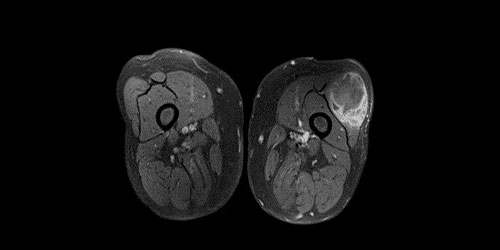

Sinovyal Sarkom

Sinovyal sarkom, nadir görülen kötü huylu yumuşak doku tümörüdür. Sinovyal sarkom çok farklı yaşlarda görülebilse de sıklıkla genç erişkinlerde (15-35) ortaya çıkar.